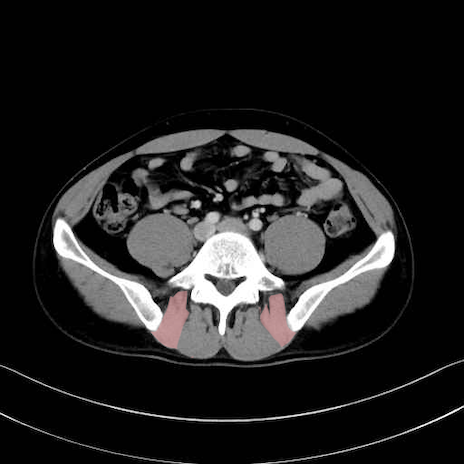

大腿方形筋 (Quadratus femoris)